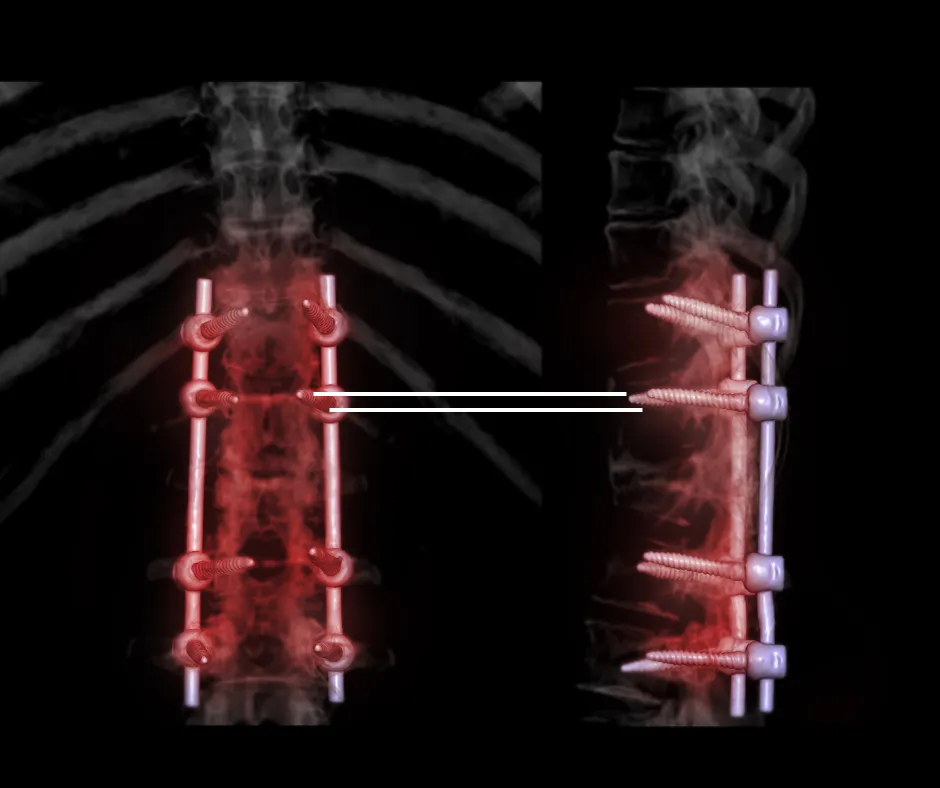

Rehabilitation bei Spondylodese / Wirbelsäulenversteifung